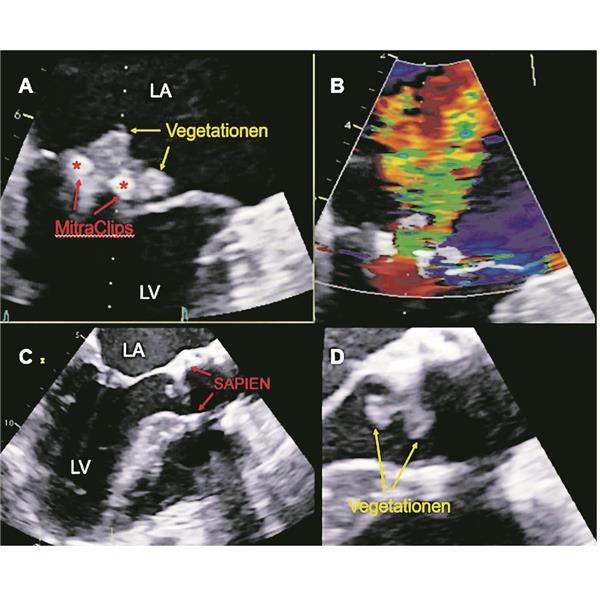

Beispiele einer Endokarditis nach TAVI und Mitralklappen-TEER

Patient 1 (A, B; männlich, 88 Jahre) entwickelte einen Monat nach Implantation von 2 MitraClips bei einem P2-Prolaps Fieber und Dyspnoe, echokardiografisch zeigte sich eine erneute schwere MI (B), die transösophageale Echokardiografie bestätigte Vegetationen um beide MitraClips (A). Nachweis von Staphylococcus aureus in den Blutkulturen. Es wurde ein chirurgischer biologischer Mitralklappenersatz durchgeführt, die histologische Begutachtung bestätigte die akute IE. Der Patient konnte am 15. postoperativen Tag entlassen werden, die Antibiose wurde für 6 Wochen nach der OP weitergeführt.

Patient 2 (C, D; männlich, 76 Jahre) entwickelte 2 Jahre nach TAVI (SAPIEN-Klappe) Fieber und Dyspnoe. Nachweis von Enterokokken in den Blutkulturen. In der transösophagealen Echokardiografie zeigten sich Vegetationen an der SAPIEN-Prothese (D). Es wurde ein chirurgischer biologischer Aortenklappenersatz durchgeführt, den der Patient gut überstanden hat. Die Antibiose wurde für 6 Wochen nach OP fortgeführt.